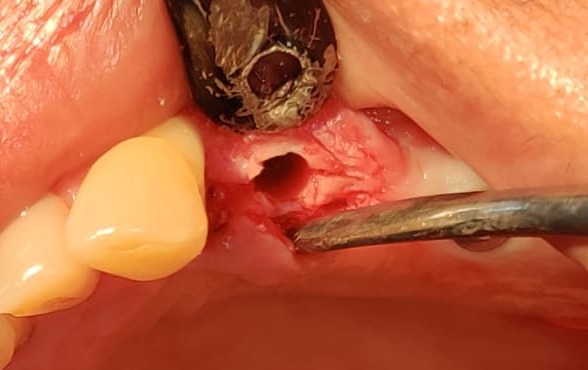

It was really challenging case. Delayed implantation with highly resorbed bone.

It was acid test for osseosure to create osteotomy without fracturing bone. and osseosure did it .

implant went with 40 NCm torque.